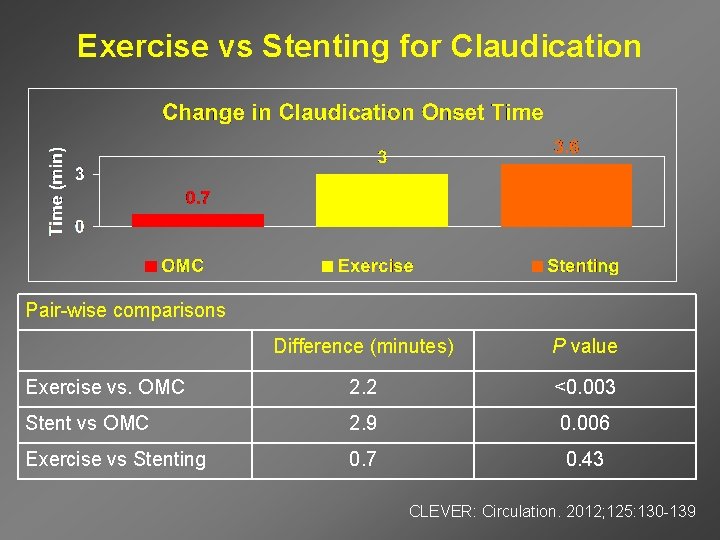

Exercise vs Stenting for Claudication Pair-wise comparisons Difference (minutes) P value Exercise vs. OMC 2. 2 <0. 003 Stent vs OMC 2. 9 0. 006 Exercise vs Stenting 0. 7 0. 43 CLEVER: Circulation. 2012; 125: 130 -139